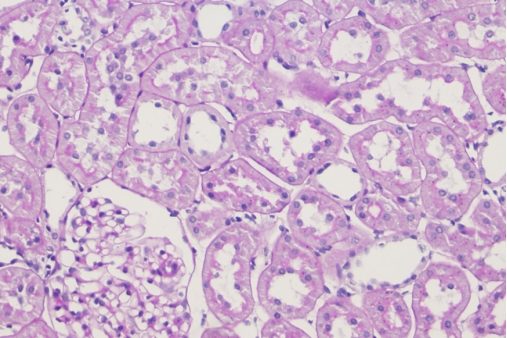

2 HE staining of paraffin-embedded renal tissue sections: Delayed or incomplete fixation results in blurred cell nuclei and poor contrast.

Common issues: Delayed or incomplete tissue fixation can result in gray and blurred cell nuclei with poor contrast in HE staining; unsatisfactory IHC results—typically, antigens are completely lost 2 hours after tissue excision.